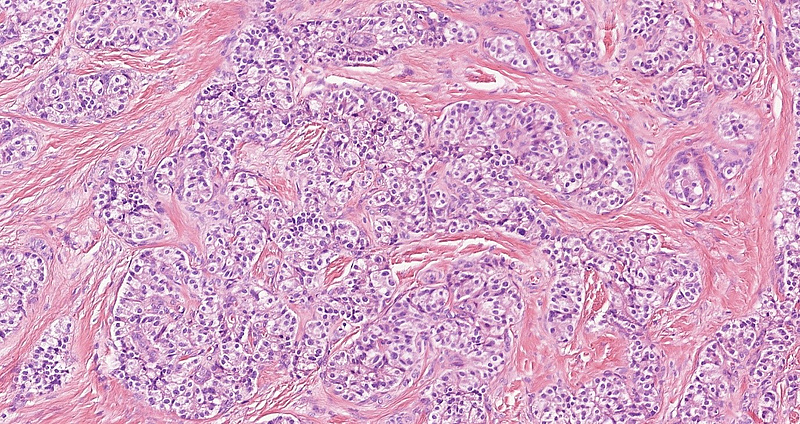

On low power, we noted a nest-forming, occasionally rosettoid tumor with expansive border (Panel A). The tumor cells were monomorphic with ample, eosinophilic cytoplasm, salt-and-pepper chromatin and occasional inconspicuous nucleoli. Mitoses were not observed. No necrosis. The stroma of the tumor consisted of exuberant, dense, hyalinic collagen with central calcification (Panel B). No lymphovascular or perineural invasion was identified. Immunohistochemistry revealed a diffuse cytoplasmic positivity for synaptophysin (Panel C), perinuclear dotlike positivity for chromogranin-A (Panel D) and diffuse cytoplasmic positivity for Insulin (Panel E). The Ki-67 labelling index was less than 1% (Panel F).